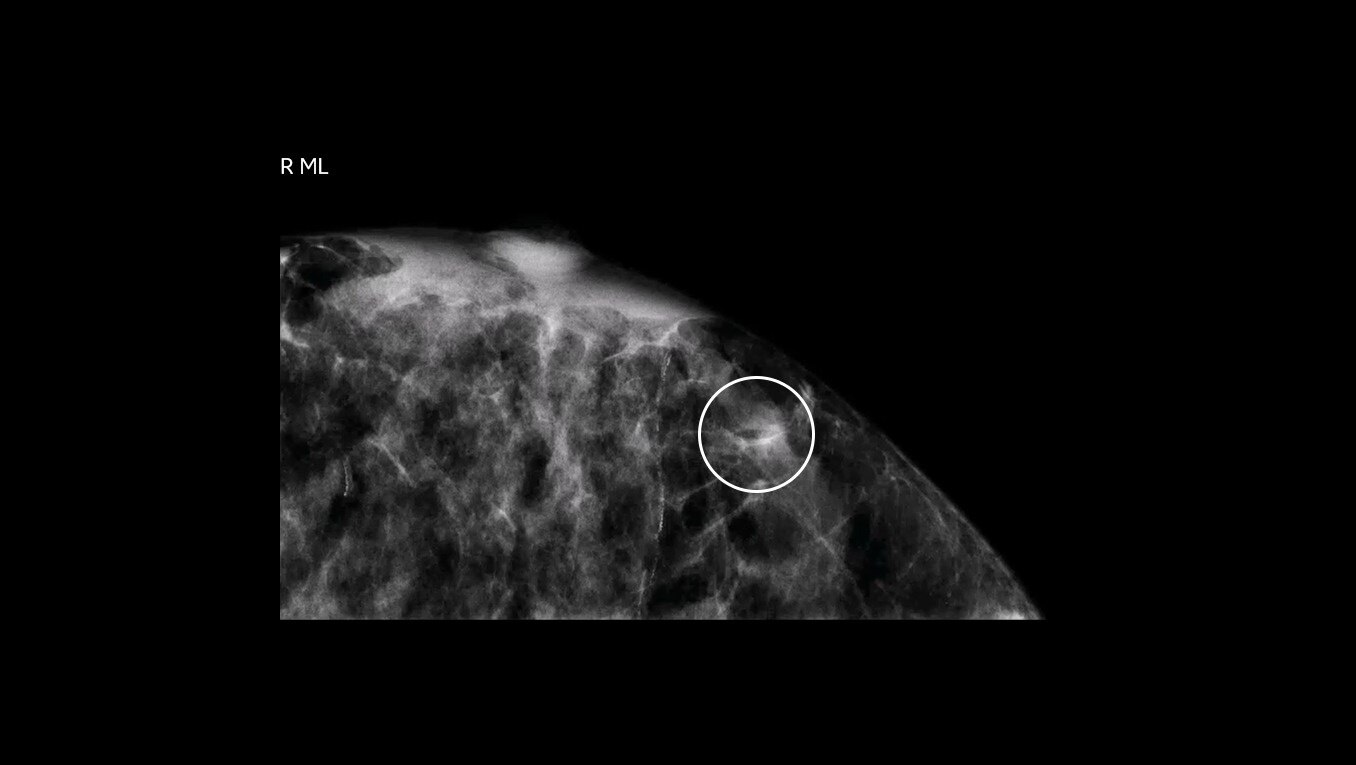

Serena Bright enables providers to see lesions using contrast-enhanced mammography (CEM) and sample with certainty. This allows patients to undergo breast biopsy exams using the same mammography equipment, in a familiar setting, with familiar staff, to help relieve some of the stress of a biopsy procedure.

Avoid the challenges of seeking correlating lesions in MRI. CEM allows you to see lesions clearly and sample with certainty with the same image guidance.

With high sensitivity and specificity, CEM helps drive accuracy in biopsy. It allows you to clearly target suspicious areas by correlating lesion locations already identified in your patient’s diagnostic enhanced mammogram.